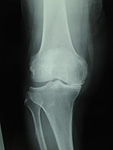

変形性膝関節症の分類

変形の進行に応じて、gradeⅠからgradeⅤに分類されます。